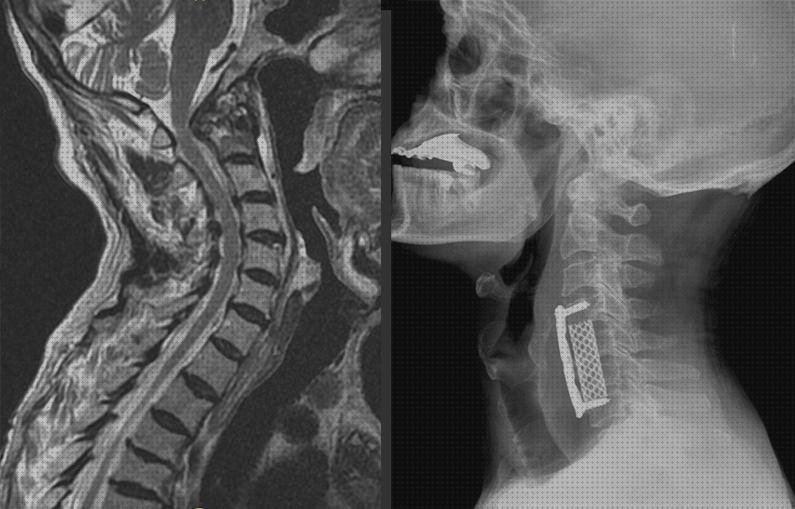

REVERSIÓN DE LA FUSIÓN CERVICAL ANTERIOR MEDIANTE LA COLOCACIÓN DE UNA